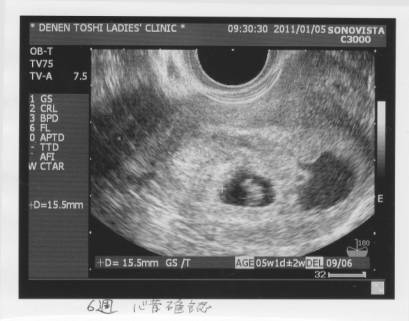

平成23年1月5日(水)

出血が見られる。

黄体ホルモン注射。